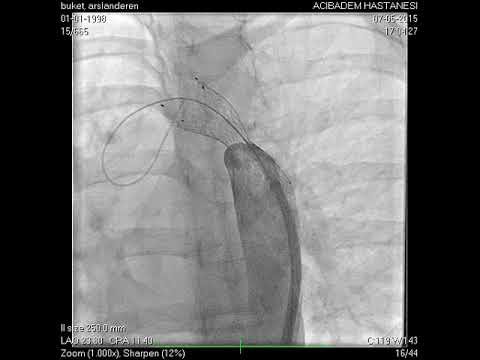

Anjiyografik İşlemler